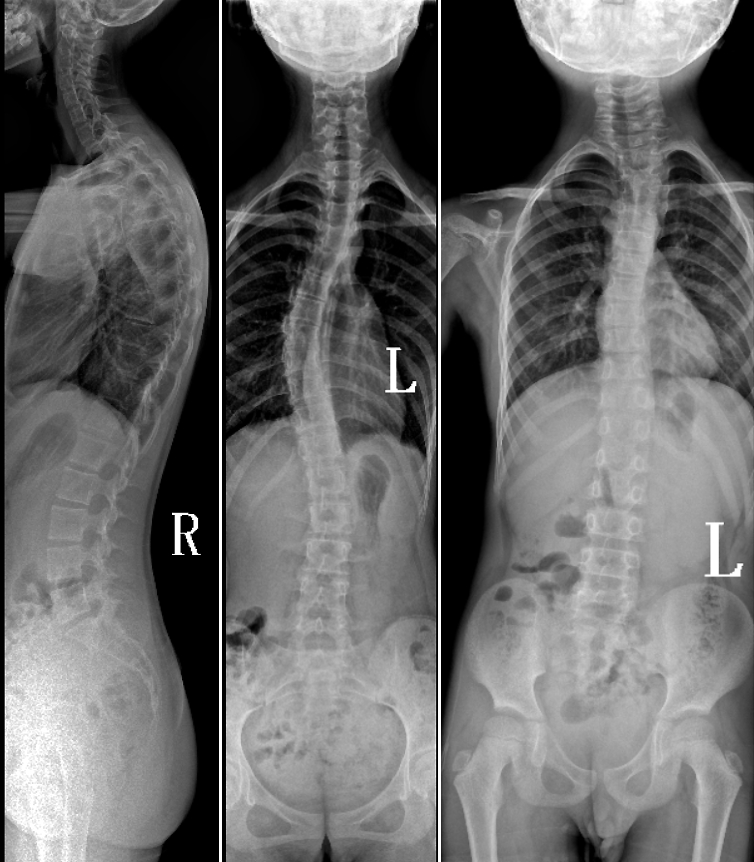

DR是臨床骨科的重要檢查手段之一。在骨科檢查中,脊柱矯形、長骨骨折、腰椎退行性病變等,需要采集脊柱、下肢全景圖像,輔助醫生臨床診斷,從而制定科學的治療方案,普愛醫療的大視野平板動態DR就像是一座橋梁,連接起現代醫療技術與當地人民的醫療需求。

普愛醫療自主研發的大視野平板動態,采用17"*34"的有效視野,一次曝光即可得到全脊柱或全下肢影像。相較于多張攝影再軟件拼接的DR設備,PLX8600解決了拼接圖像存在密度不均勻,拼接處圖像配準和放大效應等問題,給臨床帶來了真正的大視野影像解決方案。

除了常規靜態攝影外,PLX8600的大平板具備動態透視和點片功能,能夠很好地觀察復雜部位病灶,有效地抓取關鍵幀,降低患者多次攝片的概率。如:全脊柱狀態評估、長骨關節活動度、下肢靜脈造影瓣膜功能評估、消化道功能評估、脊髓造影等更多大視野臨床應用,“多面手”都能輕松應對。